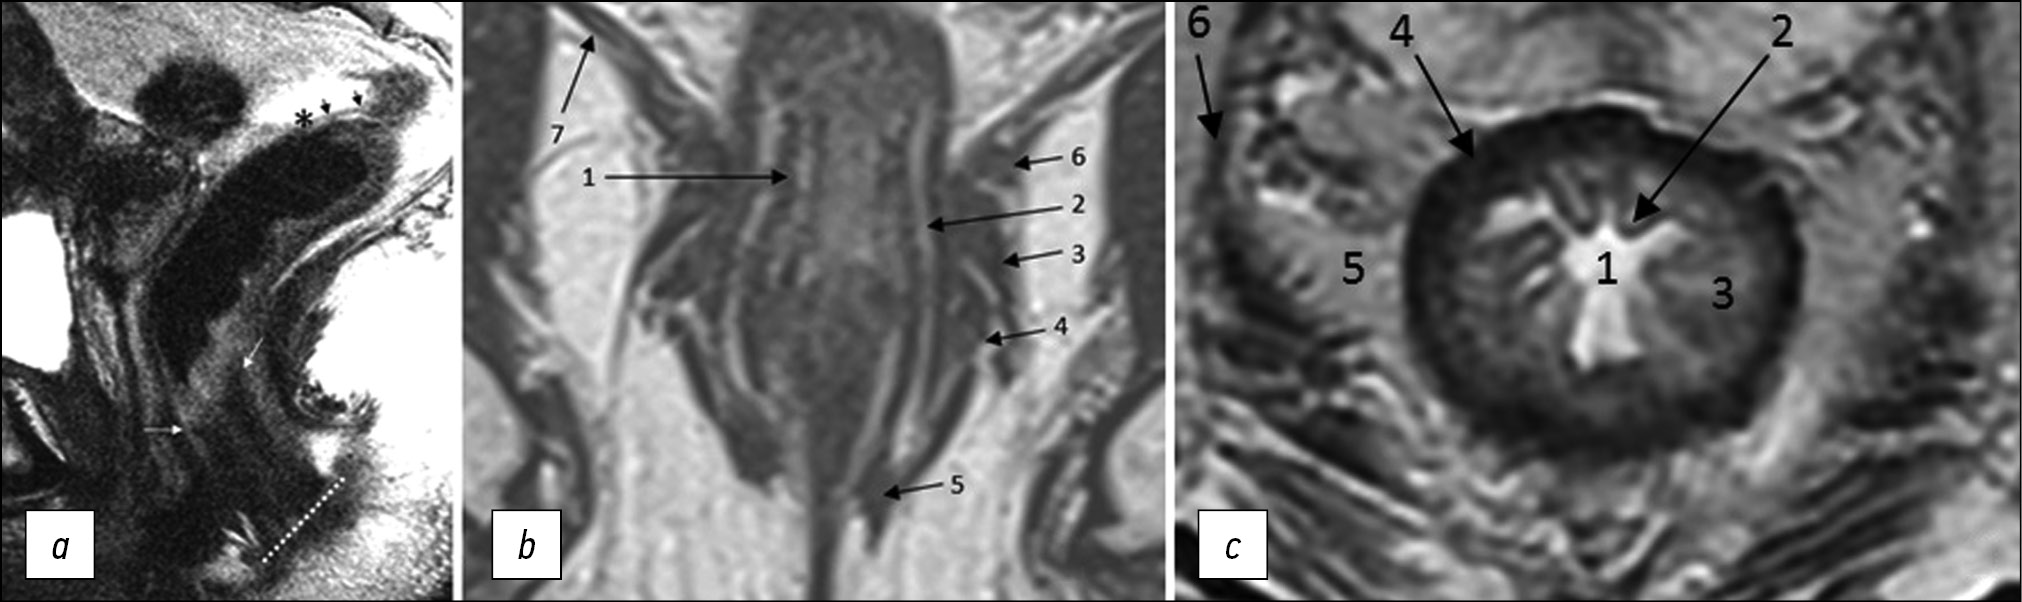

Fig. 1. MRI anatomy of the rectum on T2-WI. (a) Sagittal plane: anal edge (intersphincteric groove; dotted line); anorectal junction (angle) at the level of the upper border of the internal sphincter of the anal canal (white arrows); transitional fold of the peritoneum at the lower point of attachment of the pelvic visceral peritoneum to the rectal wall (asterisk); peritonealized part of the rectum (black arrows). (b) Coronal plane: 1, internal sphincter of the anal canal; 2, intersphincteric space; 3, deep portion of the external sphincter; 4, superficial portion of the external sphincter; 5, subcutaneous portion of the external sphincter; 6, puborectalis muscle; 7, elevator muscle of anus (levator ani). (c) Axial plane: 1, intestinal lumen; 2, mucous membrane; 3, submucosal layer; 4, muscle layer; 5, mesorectal tissue; 6 mesorectal fascia.

The internal anal sphincter is a continuation of the internal circular muscle layer of the rectum, comprising smooth muscle tissue. On MRI, it is determined by a significant thickening of the intrinsic muscle layer of the wall at the level of the anal canal (Fig. 1). The signal from the internal sphincter on T2-weighted images is slightly higher than that of the external sphincter, and with contrast enhancement, it appears more intense.

The external anal sphincter is a striated muscle, which is a continuation of the puborectal muscle, divided into three layers, such as the subcutaneous circular layer, superficial ellipsoidal layer, connected to the coccyx, and deep layer, closely connected with the puborectalis muscle (Fig. 1).

The intersphincteric space is a connective-cellular tissue space that separates internal and external anal sphincters and is characterized by a high signal on T2-WI (Fig. 1).

Mesorectal fascia is a thin fascial sheath that limits the rectum and the surrounding fatty tissue. On T2-WI, it appears as a hypointense circular line (Fig. 1). In men, the mesorectal fascia in front merges with the Denonvilliers’ fascia, while in women, it merges with the rectovaginal fascia (septum). At the back, it connects with the presacral fascia; it completely surrounds the rectum only to the level of the transitional fold of the peritoneum with its lateral and posterior parts above and only the posterior rectum at the level of the upper ampullary. Caudally, the mesorectal fascia passes into the intersphincteric space.

The muscular layer of the rectum consists of an inner circular and outer longitudinal layer, which are defined as a single hypointense layer on T2-weighted MRI images, limited internally by a hyperintense submucosal layer and externally by hyperintense mesorectal tissue (Fig. 1).

The elevator muscle of the anus (m. levator ani) is a muscle complex (Fig. 1), consisting of the puborectalis, pubococcygeus, iliococcygeus, and anal-coccygeal fibrous muscles and anococcygeal ligament. Tumors infiltrating the elevator muscle of anus are classified as T4b.

The transitional fold of peritoneum is formed at the point of transition of the peritoneum from the pelvic organs to the rectal wall, with the lower point of attachment along the anterior wall of the intestine and obliquely going up the side walls. It separates the peritonized and non-peritonized parts of the rectum. On T2-WI, it appears as a hypointense line, displaying a V-shape in the axial plane, and passes from the apex of the seminal vesicles (in men) or from the body of the uterus (in women) in the sagittal plane (Fig. 1). Lymphatic drainage from tumors located above the transitional fold of the peritoneum mainly occurs through the upper rectal and lower mesenteric lymph nodes. Tumors below the transitional fold of the peritoneum can drain through the internal iliac and obturator lymph nodes. When describing MRI findings, it is recommended to indicate the position of the tumor relative to the transitional fold of the peritoneum (completely below/crosses/completely above) [6].